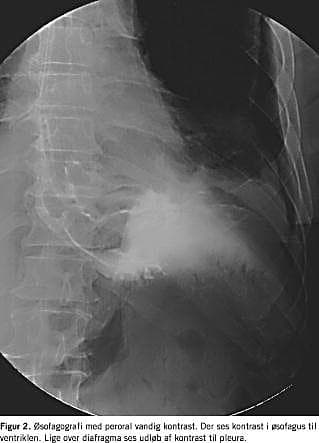

Røntgen af thorax viser hydrothorax i 80-90% af tilfældene [1]. Påvisning af føderester eller ventrikelsekret med pH < 6, stort indhold af amylase og pladeepitelceller i det drænerede materiale vil være diagnostisk, men det er en sjældent udført undersøgelse. Diagnosen stilles i de fleste tilfælde ved øsofagografi med peroral vandig kontrast (Figur 2 ).